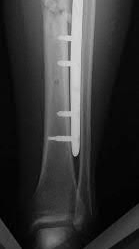

A 25-year-old female is involved in a motor vehicle collision. She presents with the isolated injury seen in Figures A through D. Her leg is swollen but her skin is intact. She has no clinical signs of compartment syndrome. Which of the following treatment options will allow for maintenance of fracture alignment and minimize the risk of soft tissue complications?

The patient presents with a closed distal third metaphyseal-diaphyseal distal tibia fracture with simple intra-articular extension. Immediate intramedullary nailing along with percutaneous fixation of the articular component provides appropriate restoration of length, rotation and alignment and minimizes the risk of wound complication.

Displaced distal third tibia fractures may be associated with simple intraarticular extension. Operative treatment of intra-articular distal tibia fractures has historically been performed with open reduction and internal fixation. Early open reduction and plate fixation of pilon fractures has been associated with high rates of infection and wound complication. In select patterns with simple articular extension, percutaneous screw fixation and medullary nailing may provide appropriate reduction with minimal soft-tissue risk.

Marcus et al. evaluated the outcomes of immediate intramedullary nailing and percutaneous fixation of simple intra-articular distal tibia fractures (AO/OTA 43 C1 and C2). The authors found excellent rates of union and alignment, however caution against broad application of this technique until more rigorous randomized studies can be performed.

Figures A and B demonstrate a distal third tibial shaft fracture with simple intra-articular extension. The axial and coronal CT cuts in Figures C and D further clarify the articular injury. Illustrations A and B demonstrate a comminuted distal third tibial fracture with simple intra-articular extension. Illustrations C and D are fluoroscopic images of the same injury after intramedullary nailing and percutaneous fixation of the articular component.